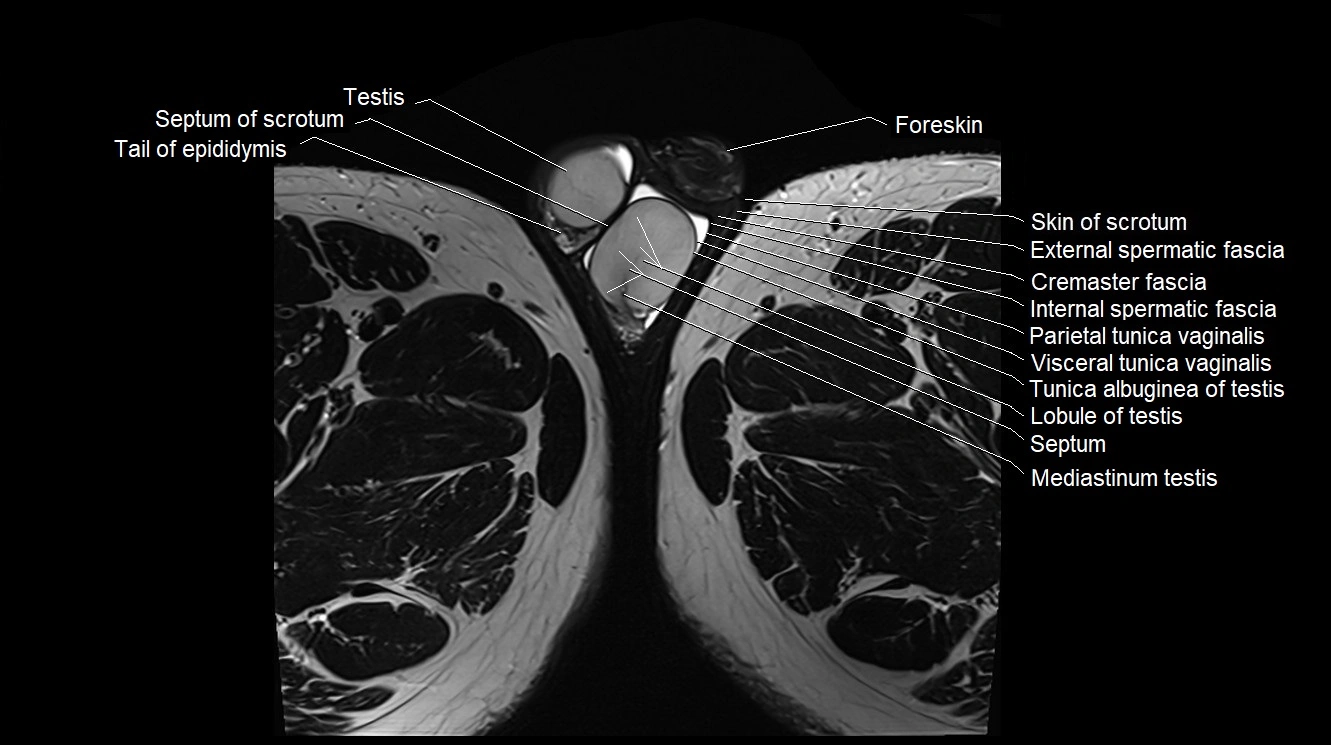

- Lobule of testis

- Mediastinum testis

- Parietal tunica vaginalis

- Septum of scrotum

- Septum of testis

- Skin of scrotum

- Tail of epididymis

- Testis

- Tunica albuginea of testis

- Visceral tunica vaginalis

- Cremaster fascia

- External spermatic fascia

- Foreskin

- Internal spermatic fascia